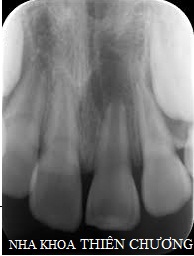

Răng sâu    Răng nha chu trầm trọng   Răng bị nhiễm trùng

Bác sĩ tiến hành thăm khám tổng quát sức khỏe răng miệng, chụp phim X-quang quanh chóp hoặc X-quang toàn hàm (nếu cần thiết) ghi nhận đặc điểm, hình dạng của những răng cần nhổ và các răng xung quanh.

X- Quang quanh chóp   X- Quang toàn hàm